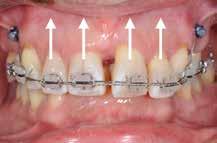

Patienttilfælde 1 (Fig. 1) er en 37-årig kvinde, henvist efter succesfuld behandling af stadie 3-parodontitis. Der er nu sundt

Før behandling

parodontium, ingen pocher over 4 mm, og både blødnings- og plakindeks er under 10 %. Patienten er motiveret for ortodontisk behandling, da hendes tænder er vandret over tid, delvist som følge af reduceret parodontium.

Der ses anterior trangstilling i begge kæber og overerupterede 1+1 og 2,1-1,2, hvilket resulterer i dybt bid med 2- tæt på ganepåbidning. Der er normale sidetandsrelationer, men der ses 5 mm horisontalt overbid (HOB) og 7 mm vertikalt

overbid (VOB). Papillen mellem 1+1 er betydeligt reduceret pga. fæstetab, og de mesialt kippede 1+1 har resulteret i en ”dark triangle”. Den facioorale funktion er for nuværende i.a. Panoramarøntgen (Fig. 1, I) viser marginalt knogletab i begge kæber og fravær af 8,7+7,8 og 8,7-8.

Objektivt anbefales behandling af det dybe bid, som ubehandlet forventes at forværres yderligere over tid. Patienten har ønske om behandling med æstetisk ortodontisk apparatur, alignere, og det vurderes muligt at behandle malokklusionen med alignere. Dog anbefales det generelt, at alignere undgås eller benyttes med væsentlige modifikationer af alignerens retention ved tandmobilitet, da dette ellers kan medføre jiggling, når aligneren tages af og på mange gange dagligt. På den anden side er der nogen evidens for, at alignerbehandling er associeret med bedre renhold og parodontal sundhed sammenlignet med fast apparatur (16).

Ortodontisk behandling af patienter med parodontitis kan ofte foretages sikkert ved at følge en systematisk tilgang, der omfatter 1) inflammationskontrol, 2) ortodontisk korrektion og 3) livslang vedligeholdelse. Inden behandlingen påbegyndes, skal parodontiet generelt være sundt med pocher på maksimalt 4 mm og et plak- og blødningsindeks under 10 %. Restfæstet skal være tilstrækkeligt til at modstå behandlingen, som udføres med kontrollerede kraftsystemer. Målet er at forbedre æstetik og opnå normal funktion, som kan vedligeholdes på lang sigt samt facilitere restaurerende behandling.

Der planlægges alignerbehandling af begge kæber med intrusion af 1+1 og 2,1-1,2, nivellering af trangstilling UK med interproksimal reduktion (IPR) (Fig. 2 A, B) og senere IPR OK for reduktion af dark triangles mellem incisiverne efter nivellering. Patienten instrueres i at benytte alignere 20-22 timer/ dag med alignerskift hver 7. dag, og patienten ses hver 3.-8. uge under forløbet. Den første alignerserie består af 16 alignere for nivellering OK/UK og IPR i UK (Fig. 2). Efter denne serie planlægges IPR mellem incisiverne i OK for reduktion af dark triangles (Fig. 3) samt yderligere intrusion af OK og UK-fronten i 12 refinement-alignere. Patienten udviser god kooperation og er meget tilfreds med alignerapparaturet, som er mindre synligt end det faste apparatur (Fig. 4).

Behandlingen afsluttes med yderligere refinement-alignere for finindstilling af okklusionen, og efter 11 måneders ortodontisk behandling er der opnået normale relationer i alle tre